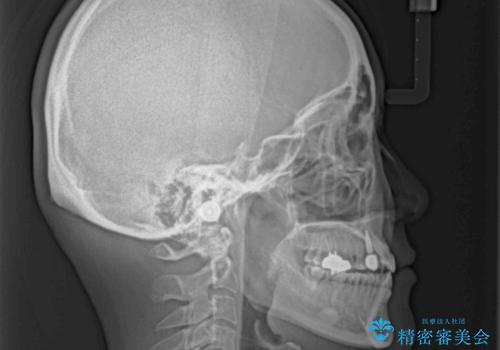

受け口で開咬を急速拡大装置とインビザラインで改善 欠損部分はインプラントにて補綴治療

矯正治療が終わるタイミングに合わせてインプラントの埋入を行っていたので、矯正治療を終了すると同時にセラミック補綴治療を行えました。

インビザラインの装着時間が不十分であったので、治療期間は長期間となりました。